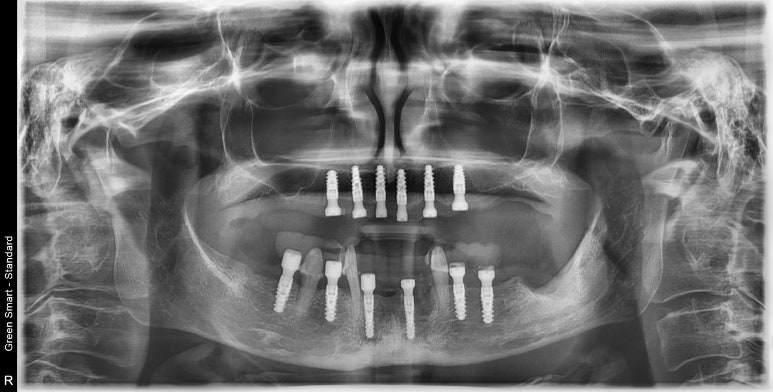

하여 상악에는 총 6개 임플란트, 하악에도 총 6개 임플란트를 심고, 국산과 외산 임플란트 중 장단점 설명을 들으시고 나서 저희 병원 시그니쳐 임플란트인 #스트라우만 BLX 임플란트로 결정하셨답니다.

상악 6개, 하악 6개 스트라우만 임플란트 식립

상악 및 하악에 총 12개의 임플란트를 식립하고 아래 3개의 치아는 고정성 임시치아를 만들어 드리기 위해 남겨두었답니다.

엑스레이 비교사진입니다.